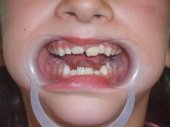

Las fracturas de los incisivos superiores en

la infancia son accidentes lastimosos que suceden con una alta frecuencia.

El tratamiento atento y cuidadoso ahorrará muchos sufrimientos

y frustraciones al paciente.